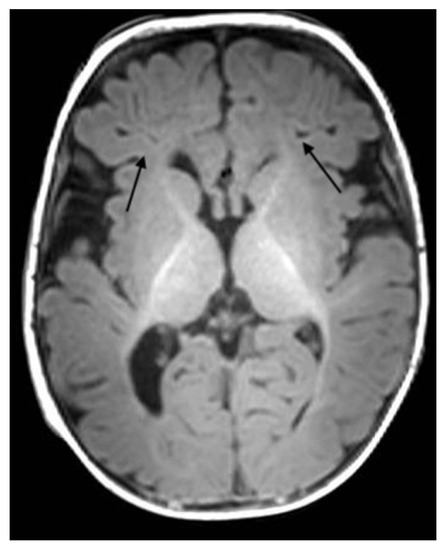

2. Case Description